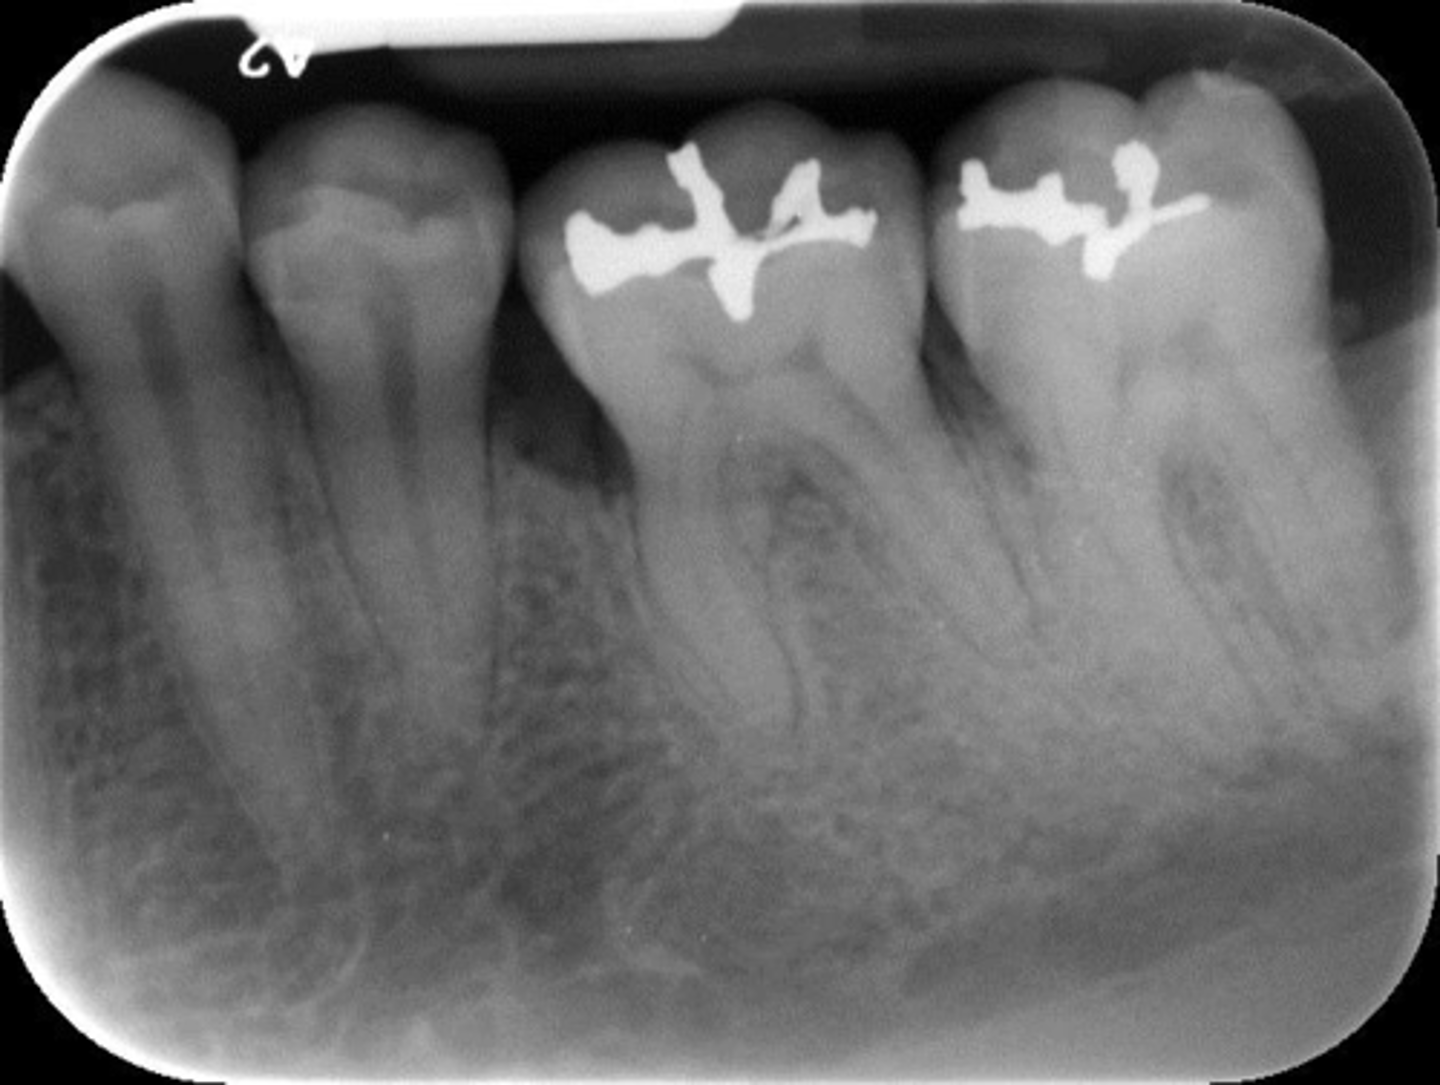

What is this projection of?

Premolars projection

Wrong film direction, backwards, positive angulation, wrong film size, no open contacts

What is this error?